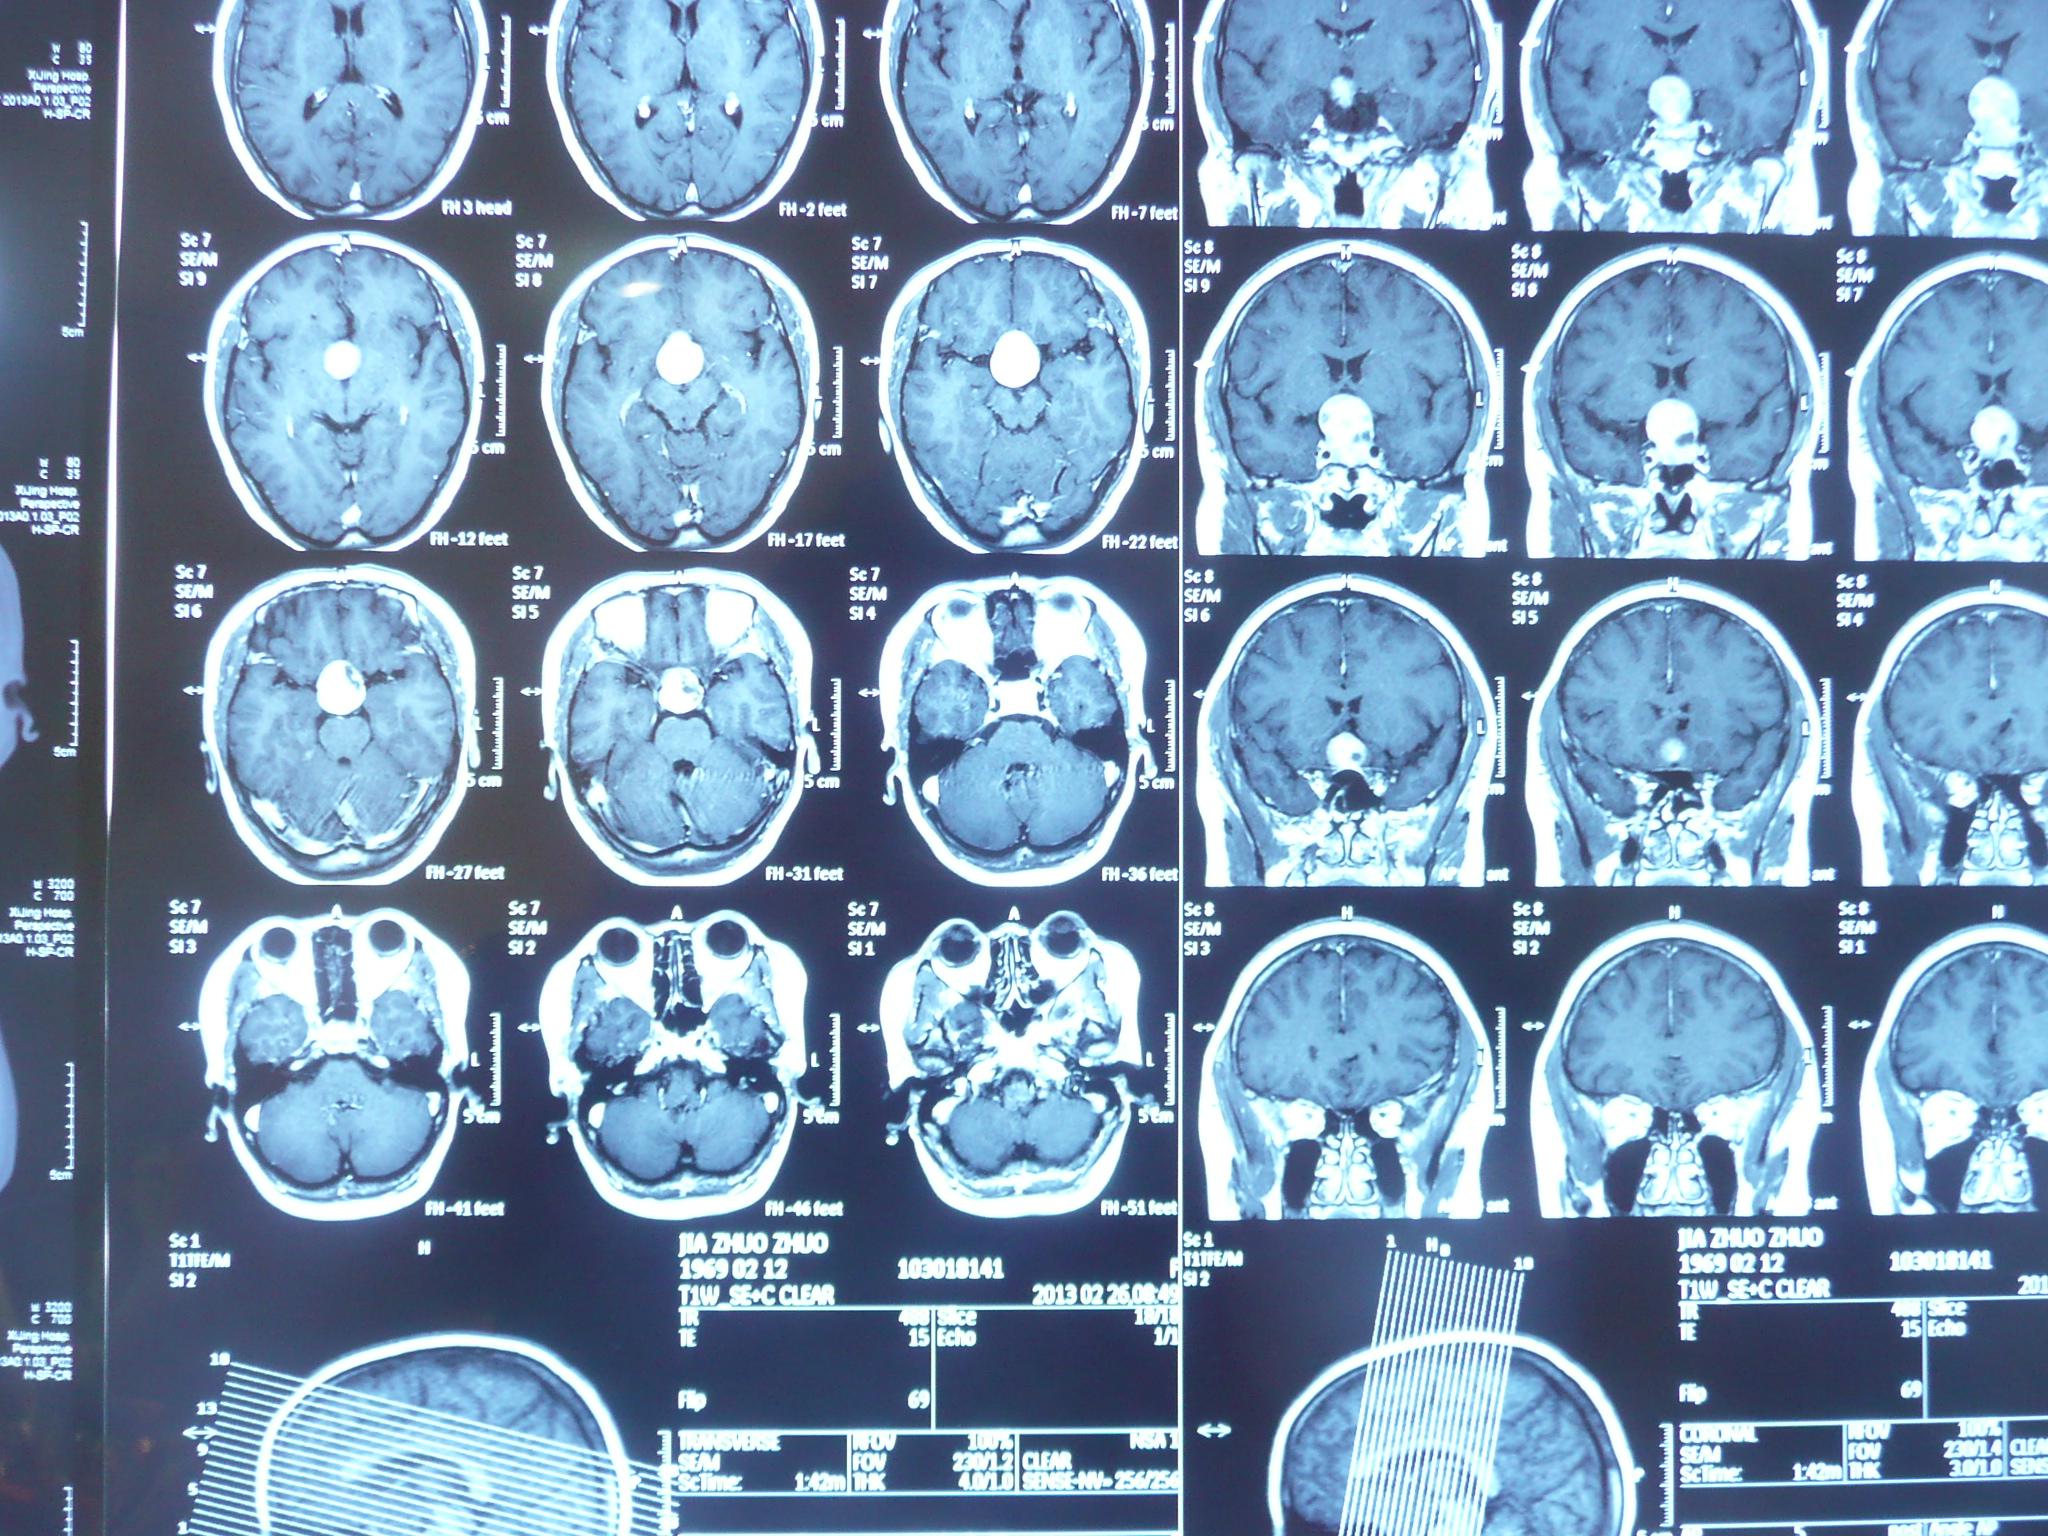

【病例讨论】前纵裂高密度,请教战友帮忙? [病例帖]

头部ct解剖及诊断基础ppt